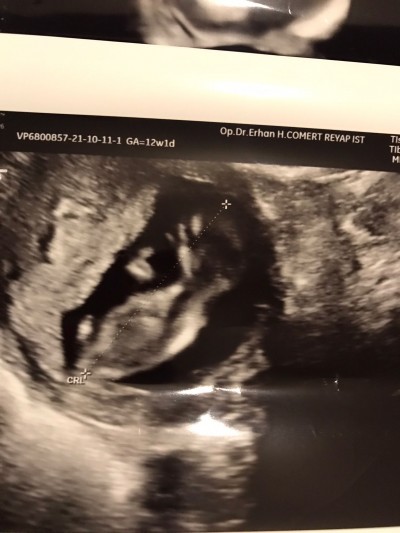

Kızlar 12+3 üm 2 gün önce doktora gittik kontrolüm yapıldı cinsiyet tahmini oluyor mu hocam dedim bir daha ki kontrole olabilir dedi çok heyecanlıyım etrafimdakiler erkek diyor eşimle ben kızcıyız ama eşimde çok fazla bi şekilde erkek hissediyor hisleri de derinden gelirse tutar yani ondan çok merak ediyorum görümcemde erkek diyor seviyorum kendisini ama erkek hissediyorum diyo eğer erkek çıkarsa ben dedim ben hissettim tuttu İşte ben demiştim diye bin kere tekrarliyor Allaha dua ediyorum Rabbim gönlümüzdekini sağlıklı nasip et hayırlı evlat nasip et sadece sen bilirsin başka kimse bilemez diyorum kız derse onun suratıni merak ediyorum çünkü ters köşe olcak yaa ne biliyim ufff sizede ultrason görüntüsü atayimda bi bakın karbonat testi Çin takvimi hep kızı gösteriyor Ayy Allahım gönlümuzdekini sağlıklı nasip etsin amin :)